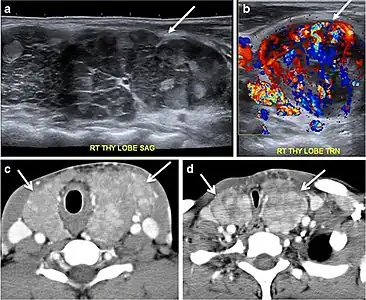

Fig. 14. A 19-year-old male patient known to have multi-nodular goiter and FNA, showing underlying Hashimoto's thyroiditis. a, b Sagittal and transverse greyscale and colour Doppler ultrasound of the neck demonstrate a hypoechoic enlarged right thyroid lobe with small hyperechoic regenerative nodules and marked hypervascularity (white arrows). c, d Enhanced axial CT scan images of the neck demonstrate a heterogeneously enhancing and enlarged thyroid gland, left more than right lobe, and the trachea is markedly narrowed.[1]